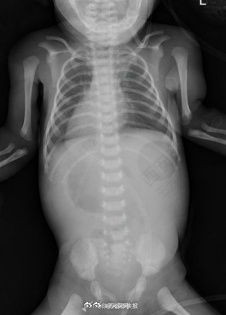

近日,西安交大一附院接诊了一名“镜面宝宝”,系36周早产儿,出生体重2.5kg,反复吐奶,腹部超声示内脏反位、十二指肠不全梗阻,心脏超声提示右位心。在辗转2家医院后仍未明确病因,且呕吐逐渐加重,随后转至交大一附院治疗。“镜面宝宝〞解剖结构特殊,加之低体重儿微创手术视野有限,手术难度很大。经历3小时手术,宝宝转入新生儿重症监护室治疗,17天后痊愈出院。(健康时报)